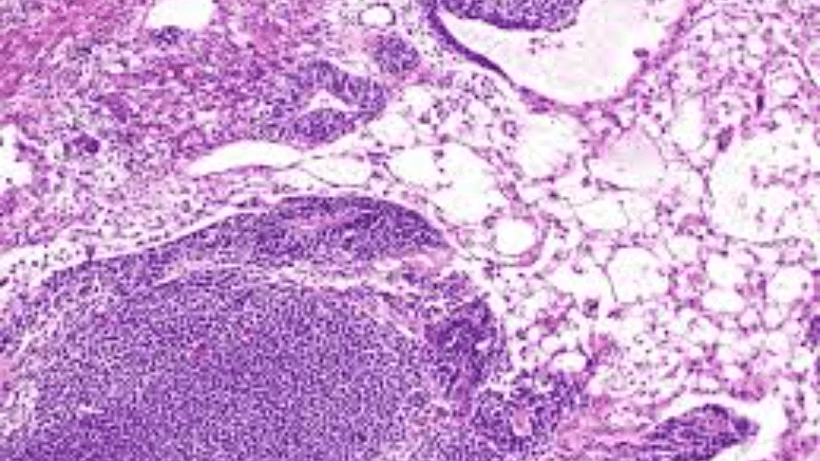

Ang mga ovarian germ cell tumor ay isang magkakaibang grupo ng mga tumor na nagmumula sa mga selula ng mikrobyo ng obaryo, ang mga selula na nagbibigay ng mga itlog. Ang mga tumor na ito ay maaaring benign (hindi cancerous) o malignant (cancerous). Kasama sa iba't ibang uri ng ovarian germ cell tumor:

1. Dysgerminoma:

Ang mga dysgerminoma ay ang pinakakaraniwang malignant na germ cell tumor ng obaryo. Madalas silang nangyayari sa mga kabataan at kabataang babae. Ang mga dysgerminoma ay lubhang sensitibo sa radiation at chemotherapy, at mayroon silang paborableng pagbabala kapag nasuri at nagamot nang maaga.

2. Endodermal Sinus Tumor (Yolk Sac Tumor

Ang mga yolk sac tumor ay mga agresibong malignant na germ cell tumor na kadalasang naglalaman ng mga istruktura na kahawig ng yolk sac ng isang embryo. Mas karaniwan ang mga ito sa mga kabataang babae at kabataan. Ang mataas na antas ng alpha-fetoprotein (AFP) sa dugo ay kadalasang nauugnay sa mga tumor ng yolk sac.

3. Immature Teratoma:

Ang mga immature teratoma ay mga tumor na naglalaman ng tissue mula sa lahat ng tatlong layer ng germ cell (ectoderm, mesoderm, at endoderm). Ang mga ito ay itinuturing na malignant at mas karaniwan sa mga kabataan at kabataang babae. Ang salitang "wala pa" ay nagpapahiwatig na ang mga tisyu sa loob ng tumor ay hindi ganap na naiiba.